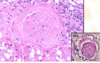

GN

thickened basement membranes are observed & increase # mesangial cells

GN

What is observed here d/t GN

incr. # mesangial cells

synechiae= adhesions betw/ glomerular tuft & the capsule

Glomerular sclerosis